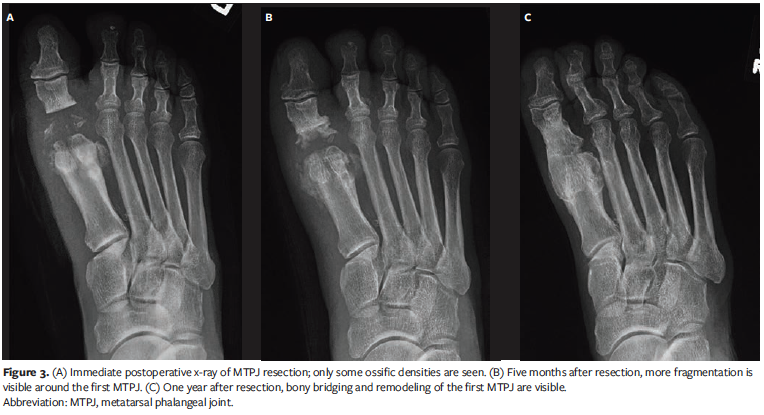

The ulcer measured 1 cm × 1.1 cm × 0.3 cm. The ulcer base had fibrogranular tissue with periwound erythema and edema. The ulcer did not probe to the bone. Deep wound cultures grew methicillin-resistant Staphylococcus aureus. The patient was admitted for intravenous antibiotic treatment and wound care. He underwent incision and drainage of the ulcer, resection of the right first MTPJ, and extensor tenotomy (Figure 3A). The patient was discharged on an oral antibiotic when the infection improved. He was placed in a CAM boot and instructed to offload. He returned 1 week later with a smaller ulcer. The ulcer worsened over the course of 2 weeks, but there were no signs of infection. The patient was admitted, restarted on antibiotics, and discharged after 5 days. The ulcer healed in 1 month.

The patient returned to the clinic 3 months later. The foot was swollen, warm, and erythematous, but there was no ulcer. He denied any trauma. Radiographs at this visit showed bone erosion around the base of the proximal phalange and the head of the first metatarsal concerning OM (Figure 3B). The authors maintained that the radiographic changes were consistent with CN, and the patient was placed on a CAM boot and advised to offload. The swelling, warmth, and redness improved in 2 months. When the patient returned to the clinic 6 months later, the radiographs showed complete coalescence of the first MTPJ (Figure 3C).